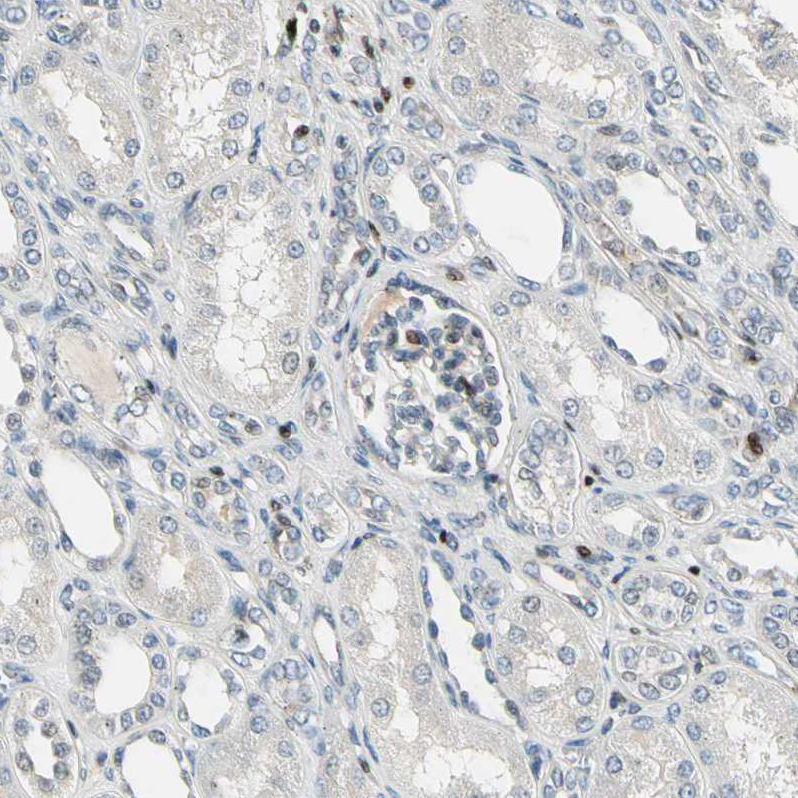

Immunohistochemical staining of human skin shows moderate to strong nuclear positivity in keratinocytes.